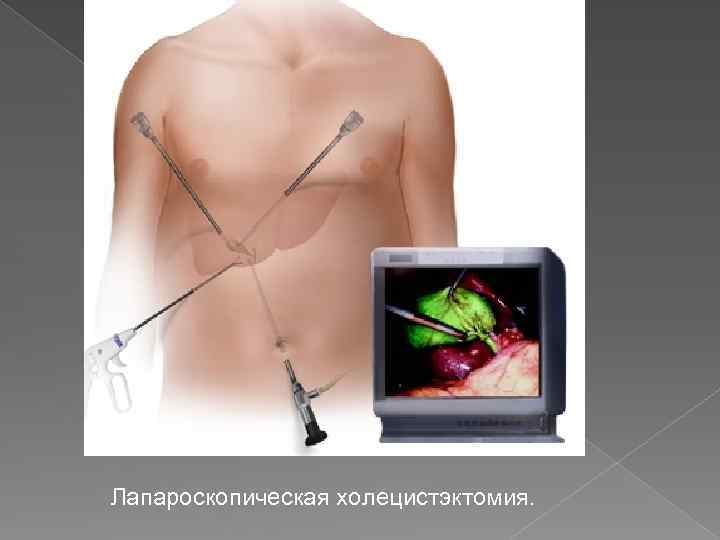

Лапароскопическая холецистэктомия.

Лапароскопическая холецистэктомия.

На рисунке схематично показан принцип операций, проводимых по методу единого доступа. Для такого вида лапароскопическ их операций требуется всего один разрез, который производится через пупок.

На рисунке схематично показан принцип операций, проводимых по методу единого доступа. Для такого вида лапароскопическ их операций требуется всего один разрез, который производится через пупок.